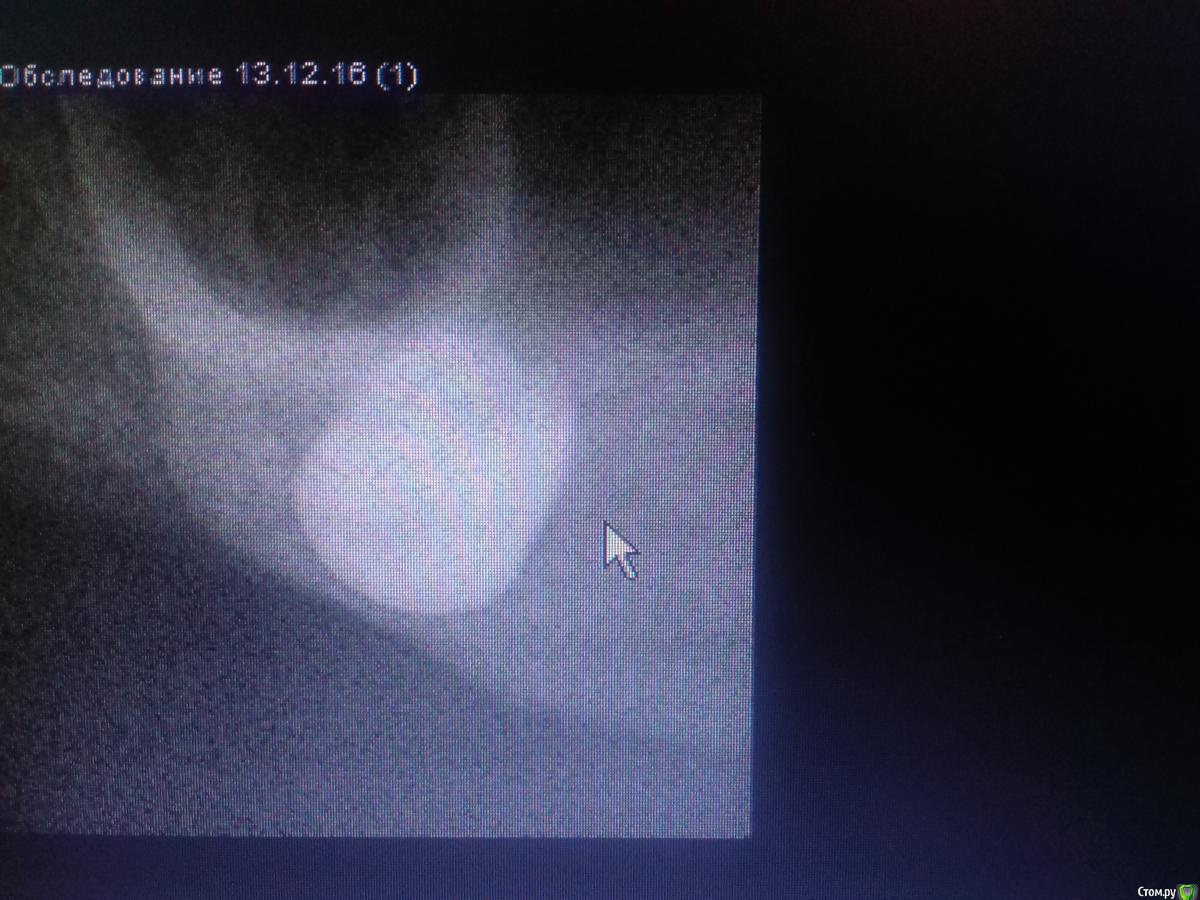

Jurai Опубликовано 26 декабря, 2016 Автор Поделиться Опубликовано 26 декабря, 2016 Как вообще впечатления от Адина?Я скажу откровенно - двойственные впечатления. Да, непафосно, да, просто, да, бывают резорбции по шейке. Но за три года, что я с ними работаю, в минусе два, ставлю почти исключительно Swell. Один вывернулся при вот такой картине Второй убрала при такой, трепаном еле выпилила, полчаса возиласьЕдинственное, я их ставлю только там, где можно хоть саморез по гипсокартону ввернуть и он интегрируется, то бишь, в идеальные условия. Ссылка на комментарий